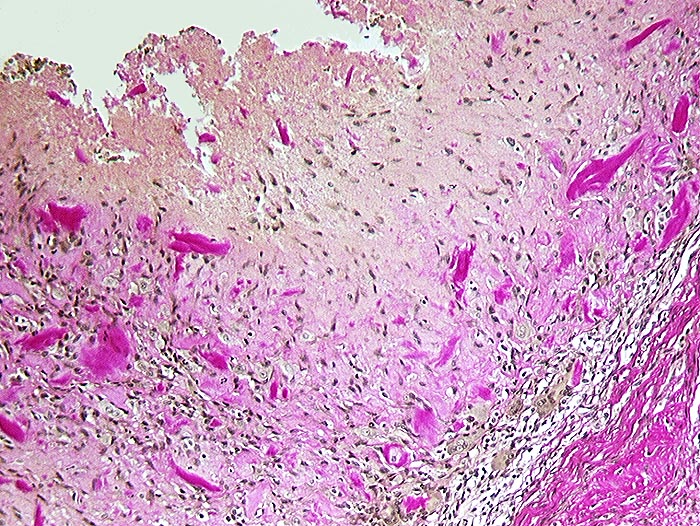

Detritussynovialitis

Entzündung / Reparatur

Synovialis

Knochen, Knorpel, Gelenke

Anstelle des Epithels finden sich avitale Knochensplitter eingebettet in Fibrin. Daran angrenzend Granulationsgewebe mit zahlreichen Fremdkörperriesenzellen.

Arthrose des Hüftgelenkes.

Histologie